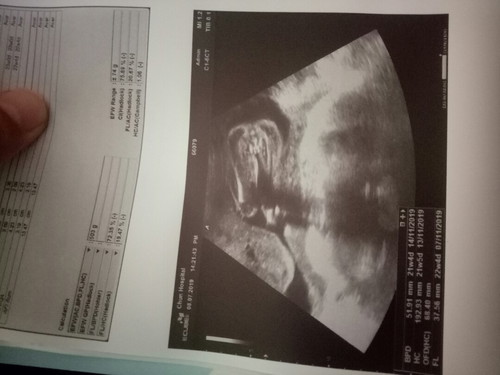

เพศ

ใครพอจะรู้มั้งว่าเพศอะไรเราดูไม่เป็น

บางทีก้อมองเป็นกลีบผู้หญิง แต่มองอีกทีก้อเหมือนอัญฑะของผู้ชายค่ะ

ไม่มีติ่งออกมาจากหว่างขา น่าจะผญ.นะคะ

ของเรานอนแบบนี้เลย ผู้หญิง จ้า

น่าจะผญ นะ อันนี้ของเราได้ผช.

ผู้หญิงคะกลีบๆไม่มีตอ

น่าจะ ผู้หญิงนะค่ะ

ผญ.ค่ะ เป็นกลีบๆ